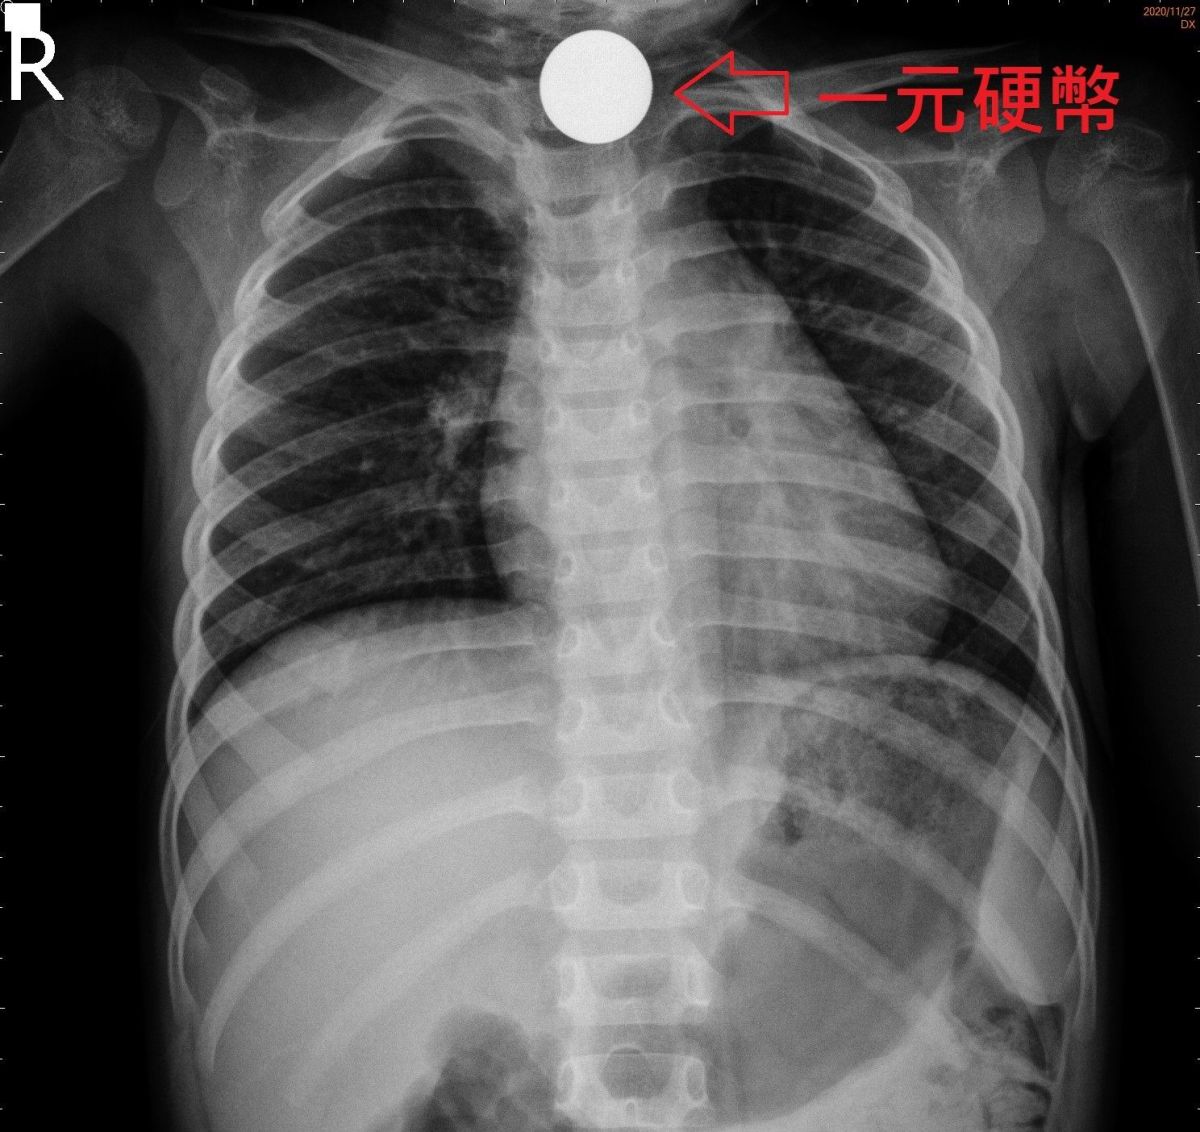

家住羅東2歲8個月的薛小妹妹玩耍時不慎吞下兩枚壹元硬幣,媽媽發現後趕緊將孩子送到聖母醫院急診室,照X光發現硬幣卡在頸部食道下不去,心慌的媽媽焦慮不知所措,拜託醫生想想幫法。

當天值班的腸胃科醫師王威迪與媽媽討論評估後,採取較有挑戰性但能快速解決問題的方法「胃鏡夾除術」,短短10分鐘立馬解除危急警報,幼童終於不再哭鬧而得以舒服喘息,同時也緩解媽媽的焦慮。